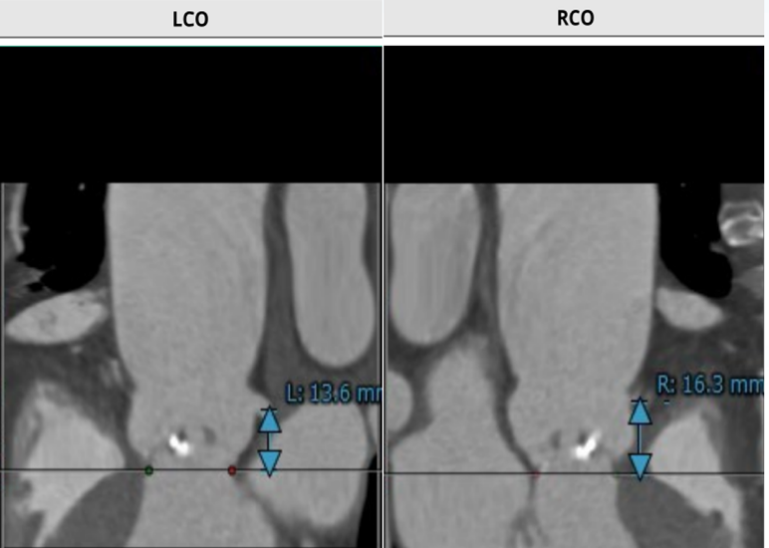

该名患者为Type 0型二叶瓣,右冠窦轻度钙化。瓣环最短径为20.0mm,最长径为27.7mm,平均瓣环直径为23.8mm。升主动脉较宽,平均直径40.5mm。左冠开口高度13.6mm,右冠开口高度16.3mm,冠脉阻塞风险低。外周血管钙化轻,入路情况较佳。FEops分析推荐匹配26mm瓣膜。

该名患者为三叶瓣,右冠窦轻度钙化。瓣环直径为23.2mm,周长为72.9mm。左冠窦中重度钙化。升主动脉稍增宽,平均直径34.0mm。左冠开口高度13.3mm,右冠开口高度15.1mm,冠脉风险低。外周血管钙化轻,入路情况较佳。